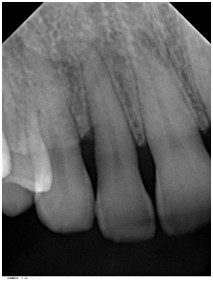

A 42- year-old white female with a non-contributory medical history was referred in May 2014 for a periodontal examination and treatment and specifically for a localized increasing pocket depth on maxillary right lateral incisor which had an initial PD of 9 mm on the disto-palatal aspect and Miller Class I mobility with BOP (Table 1). Bone loss, as determined by the radiograph (Figure 1) was an angular defect. The patient’s oral hygiene and plaque control were very good.

Figure 1 Pretreatment radiograph of tooth #7 with angular bony defect on the distal aspect.